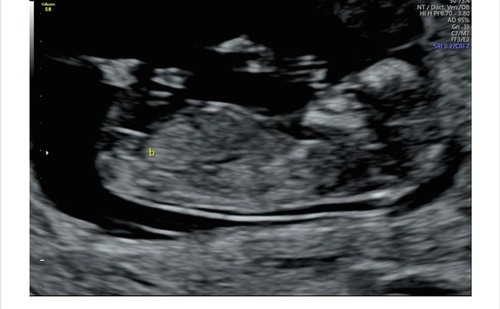

Echo met 12 weken, wat denken jullie? Met 11 weken dacht ik duidelijk een nub te zien wat dan een meisje zou zijn, maar deze zie ik het niet 🙈

Sorry, ik heb echt geen flauw idee waar ik hier naar kijk 🙈

Oops ik had de verkeerde foto geüpload, dit is de juiste 😳